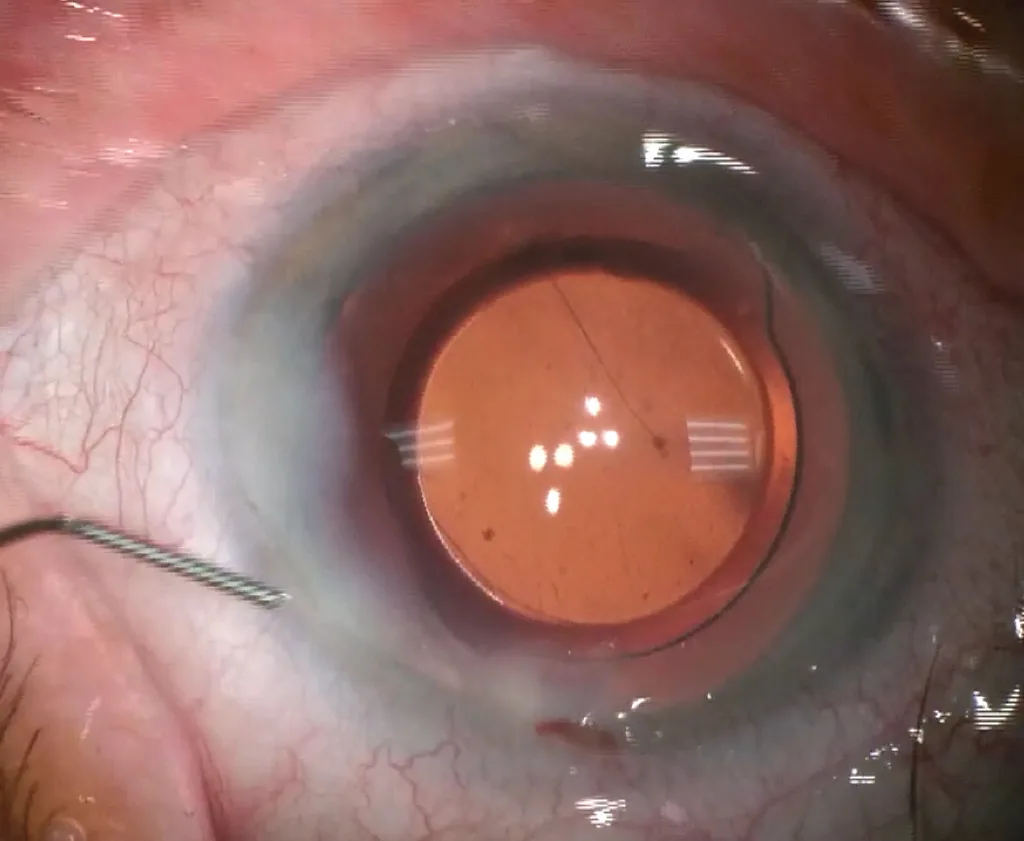

Cette cohésion est optimisée par l’hydrosuture, qui consiste à injecter du BSS (balanced salt solution) en fin d’intervention, à l’aide d’une canule fi ne de type Rycroft, à chaque extrémité de l’incision, donnant un aspect blanchâtre périincisionnel par œdème localisé induit (figure 3.8).

Figure 3.8. Hydrosuture.

Ce geste est également indiqué au niveau de l’incision de service. Dans les rares cas d’incision non étanche (par exemple, dans les cas de manœuvres excessives ou de berge rétractée par brûlure rétinienne), il est nécessaire de placer une ou plusieurs sutures cornéennes par Nylon 10-0 à nœud enfoui.

Figure 3.10. En fin de phacoémulsification, élargissement d’une incision de 1,8 à 2,2 mm avant insertion d’un implant hydrophobe.